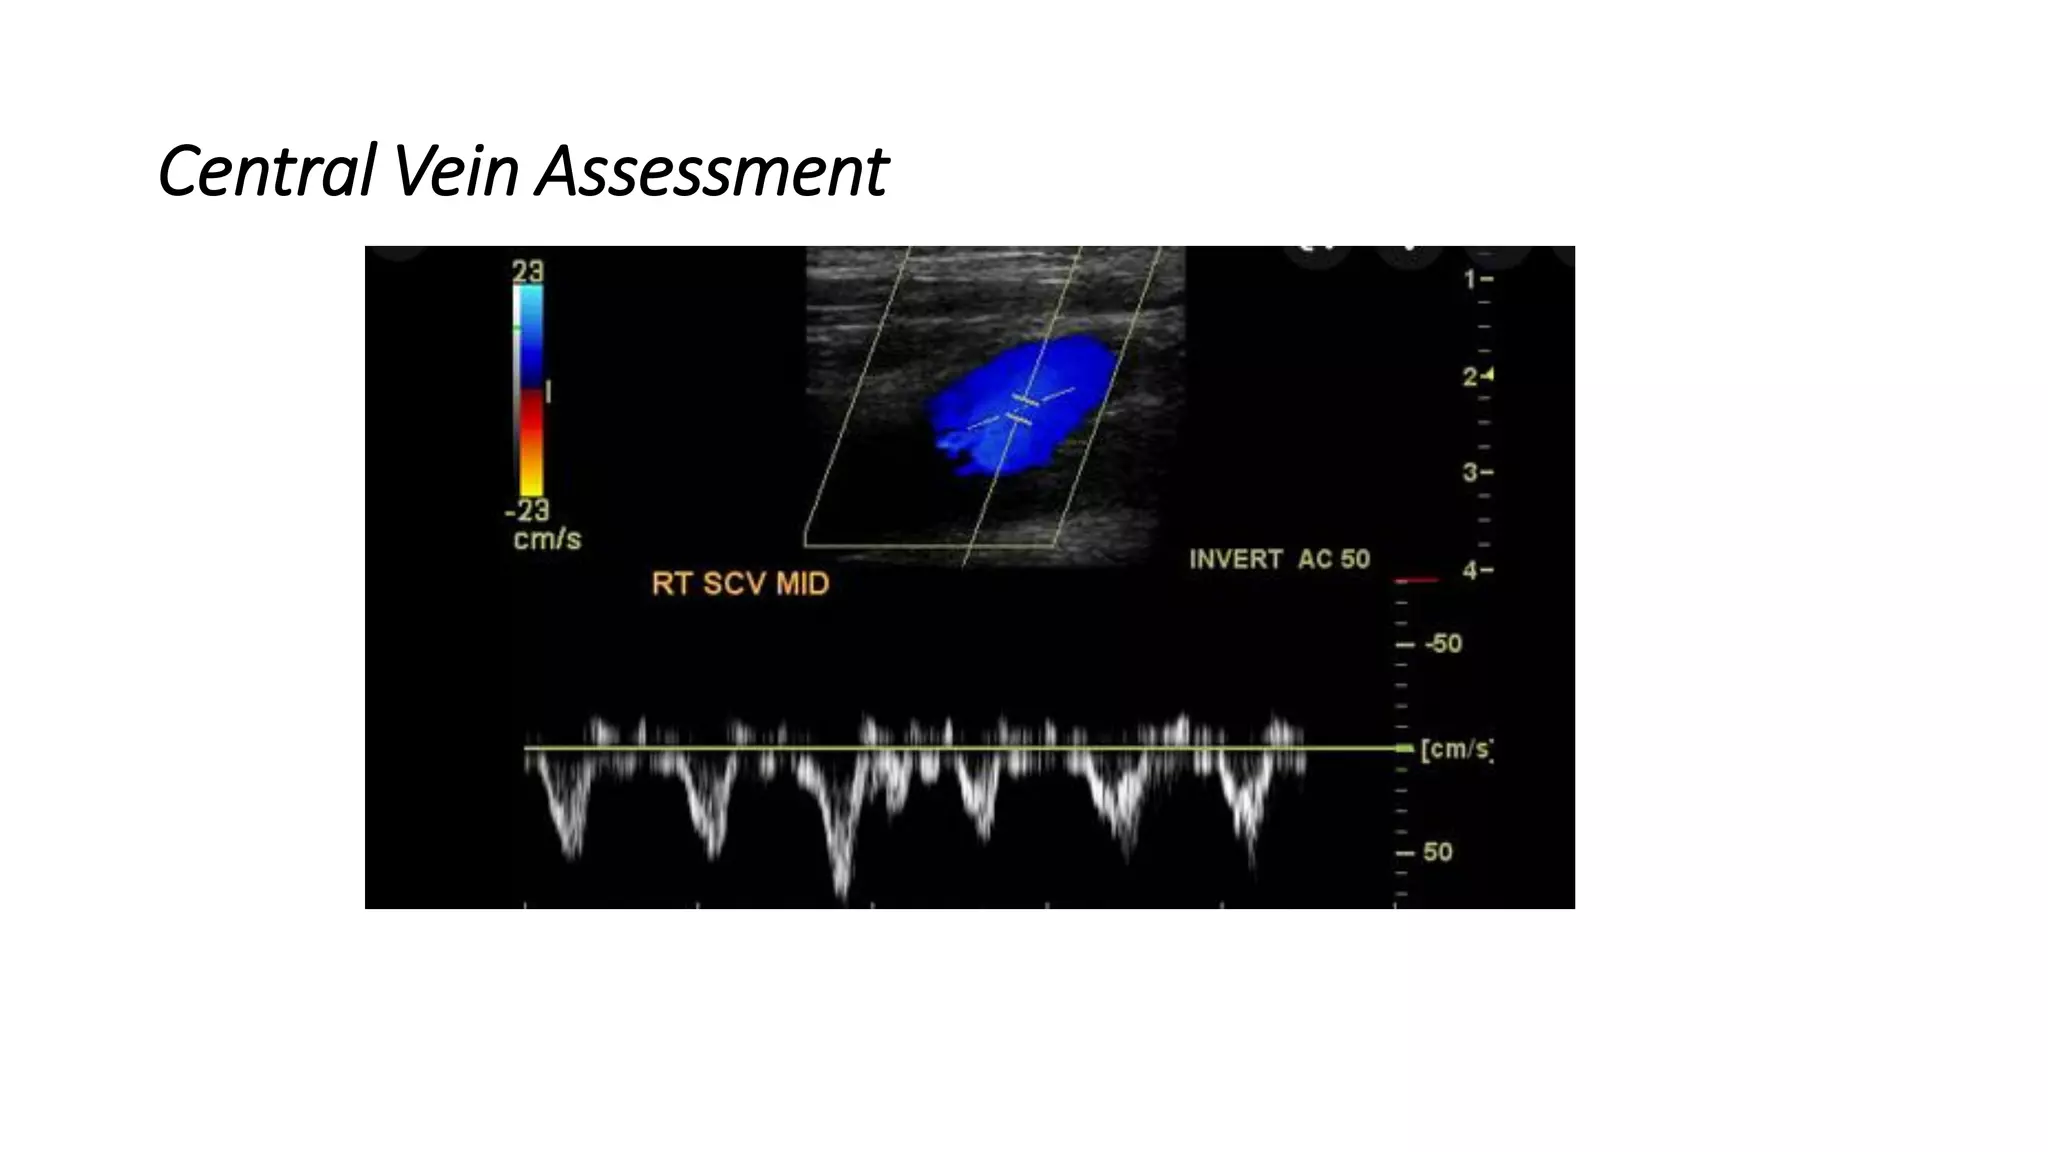

Ultrasound vascular mapping uses ultrasound to examine arteries and veins in the arms before dialysis access placement. It assesses vessel diameter, wall characteristics, blood flow, compressibility, and identifies the best vessels. The mapping examines arteries for internal diameter and wall appearance, uses Doppler to evaluate blood flow, and may check for calcification. It also assesses superficial arm veins for caliber, depth, wall appearance, distensibility, course, patency, and presence of collaterals to identify the best vessel options for dialysis access. A vein mapping worksheet is used to report the ultrasound findings.